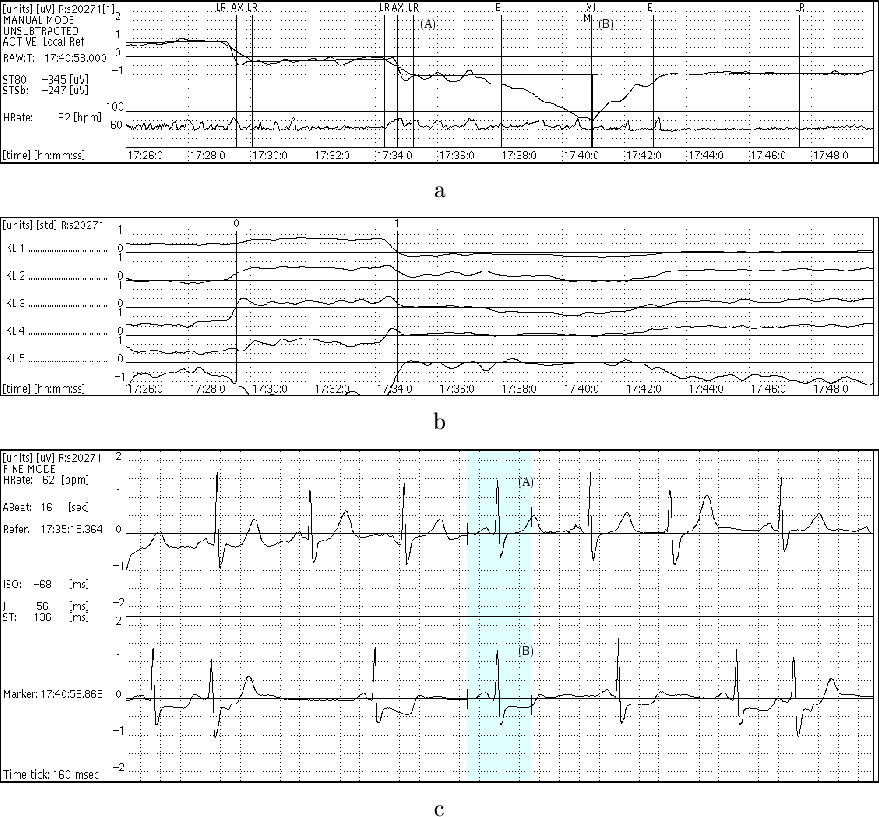

The first task faced by the expert annotators was to mark the locations of the PQ junction (the isoelectric level) and the J point, based on 16-second averaged cardiac cycles chosen at frequent intervals throughout the recordings. These marks serve as guideposts for the automated ST level measurement algorithm that performs the next step. The experts then examine the time series of ST level measurements in order to locate and to mark a set of local reference points (marked as LR in the upper panel of the figure). These are used to construct a piecewise linear baseline ST level function, which may vary over time as a result of body position changes or other factors unrelated to ischemia, especially in subjects with prior myocardial infarctions. Axis shifts reflect body position changes, and are usually most apparent in the QRS complexes (note the changes in the QRS principal components, KL1 - KL5, in the lower panel of the figure). By contrast, when ischemic ST changes occur, they are most apparent in the principal components of the ST segment (see the lower panel in this screenshot). Local references are placed before and after each such episode, and the episodes are annotated next. During this process, the expert annotators have the option of viewing either the ST level time series or the ST deviation time series (formed by subtracting the baseline ST level function from the uncorrected ST level time series), as shown in the upper panels of the two screenshots. For further details, see reference 4 below.